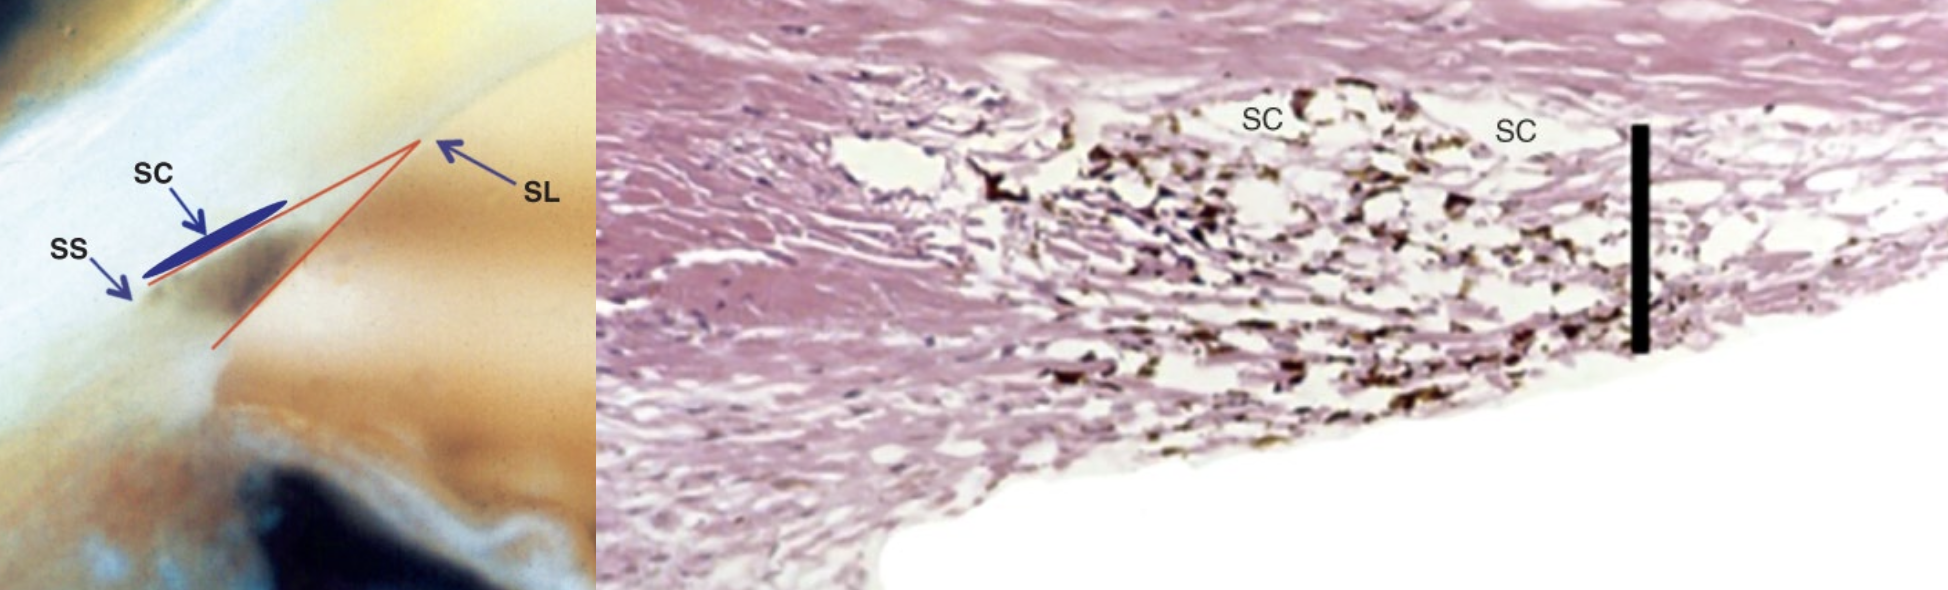

Gonioscopy

What is gonioscopy and why is it used?

→ allows clinicians to see around the cornea to view the angle tissues of the eye with goniolens or gonioprism

b/c angle structures can’t be seen directly with a slit-lamp b/c they’re covered by the perilimbal sclera

Where is pigmentation found in older normal eyes, and how does it appear during gonioscopy?

found in the posterior portion of the TM that drains directly into Schlemm’s canal

appears as an “extra” pigmented band in older eyes

In a gonioscopic (macrophotograph) view of the angle of the eye, what five lines or structures can be seen?

Schwalbe’s line

Anterior (non-flow) meshwork - “beginning of triangle,” less flow

Posterior (flow) meshwork - “base of triangle,” more flow (wider area)

Scleral spur

Ciliary body band